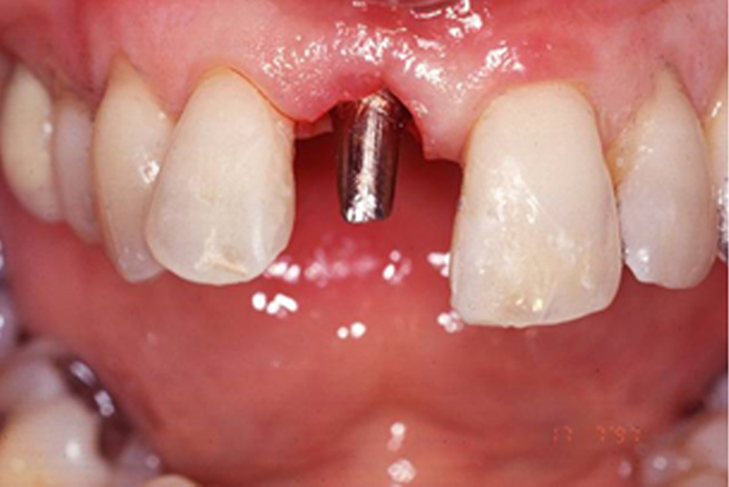

Flapless Implant Placement: Key Details

Definition: Implant placement without lifting gum tissue, minimizing invasiveness.

• Guided Access: Small punch made for direct bone access.

• Implant Placement: Implant inserted through minimal access with high precision.

• No Drilling: Avoids drilling, preserving bone and reducing trauma.

• No Flap Elevation: Eliminates soft tissue detachment, ensuring no bleeding.

• No Future Bone Loss: Maintains bone structure and soft tissue integrity.

• Accelerated Healing: Preserved blood supply leads to rapid recovery.

• Reduced Treatment Time: Minimally invasive approach shortens procedures.

• Minimized Trauma: Soft tissue remains largely undisturbed.

• Improved Esthetics: Soft tissue contour is maintained.

• Better Post-Op Comfort: Less discomfort and swelling.